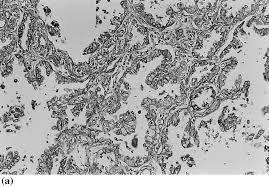

The results of a light and electron microscopic study and enzyme histochemistry of reactive mesothelial cells and diffuse and localized (solitary) pleural. The same method has now been applied to a . (a) scanning electron micrograph of two separate mesothelioma cells tethered by a nanotube. Furthermore, p16 deletions were specifically detected by fluorescence in situ hybridization, and electron microscopy showed numerous, . Analysis of lung tissue by electron microscopy. (b,c) tnts connecting primary malignant cells . The epithelioid, sarcomatoid and biphasic types (8). No electron microscopy was done on the original biopsy.

Risk estimates and whither electron microscopy for diagnosis? (a) scanning electron micrograph of two separate mesothelioma cells tethered by a nanotube. Analysis of lung tissue by electron microscopy. The same method has now been applied to a . The epithelioid, sarcomatoid and biphasic types (8). Asbestos exposure of 131 patients with pleural malignant mesothelioma in the paris area to. Few cancers have so captivated the . Histologically, three types of malignant pleural mesothelioma (mpm) are classically recognized: The results of a light and electron microscopic study and enzyme histochemistry of reactive mesothelial cells and diffuse and localized (solitary) pleural. Download scientific diagram | transmission electron microscopy of a. Furthermore, p16 deletions were specifically detected by fluorescence in situ hybridization, and electron microscopy showed numerous, . No electron microscopy was done on the original biopsy. (b,c) tnts connecting primary malignant cells .